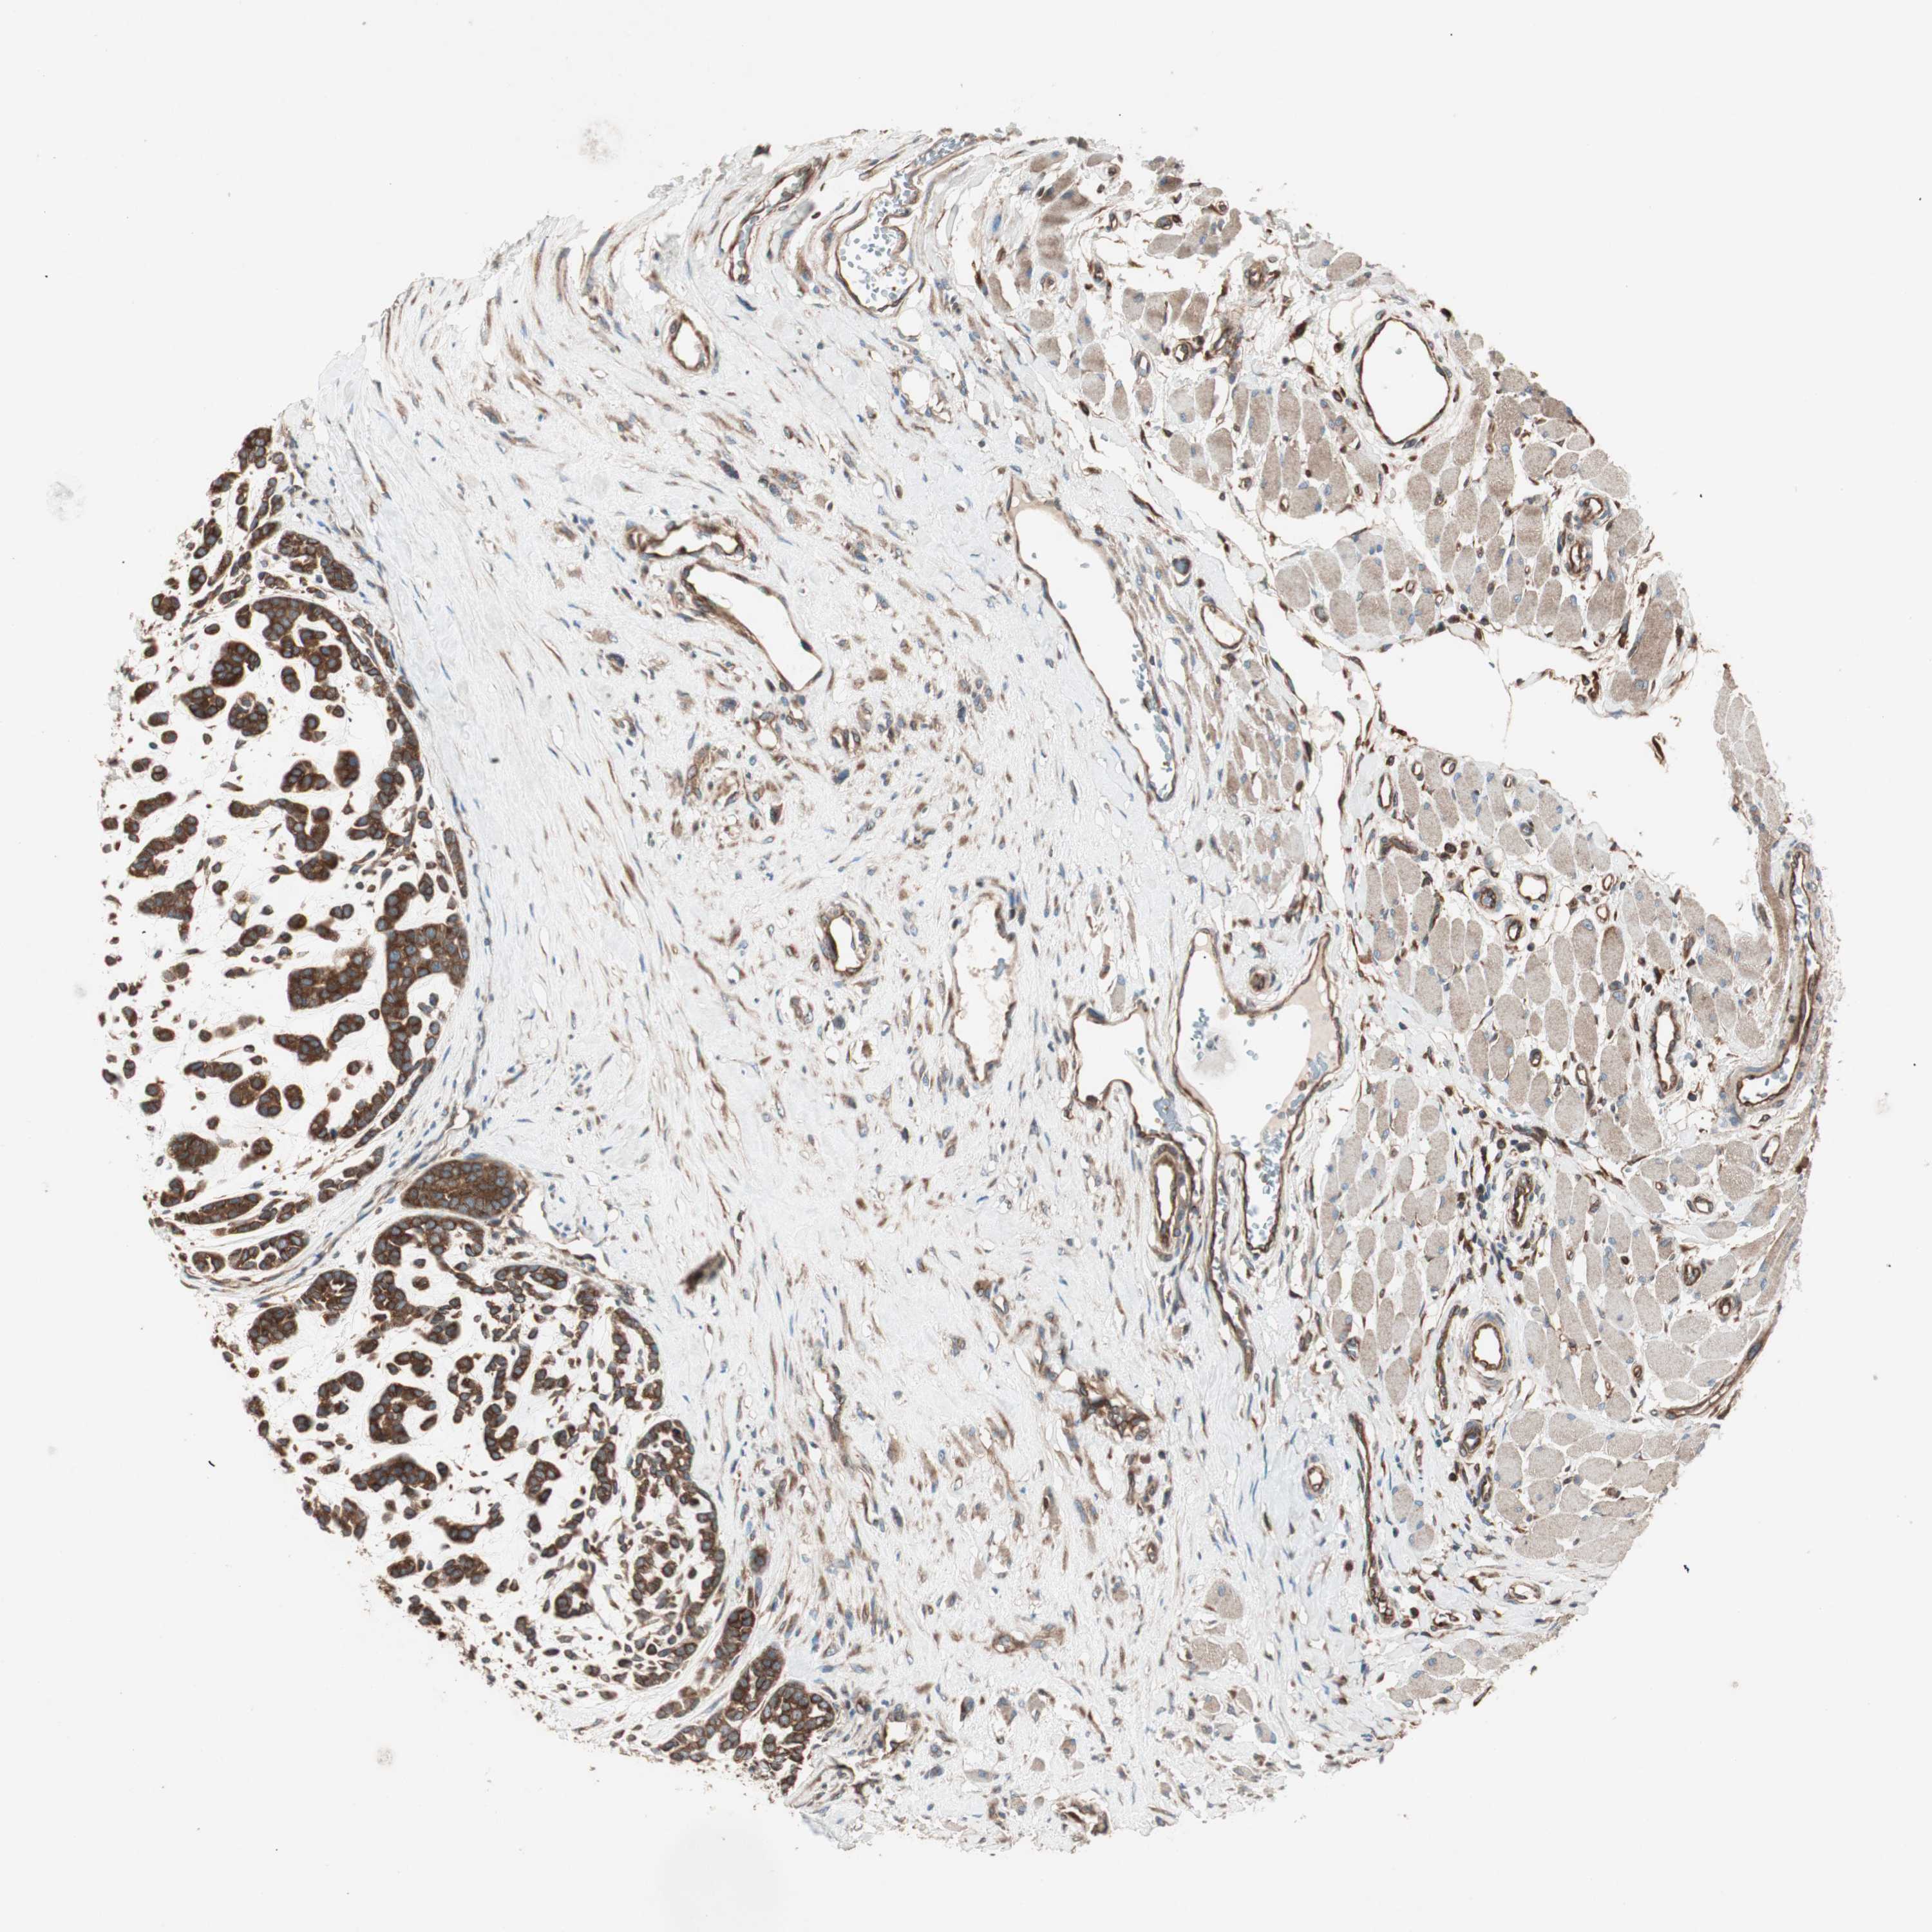

HEAD AND NECK CANCER - Protein expressioni

A mouse-over function shows sample information and annotation data. Click on an image to view it in a full screen mode. Samples can be filtered based on level of antibody staining by selecting one or several of the following categories: high, medium, low and not detected. The assay and annotation is described here.

Antibody stainingi

Antibody staining in the annotated cell types in the current human tissue is reported as not detected, low, medium, or high, based on conventional immunohistochemistry profiling in selected tissues. This score is based on the combination of the staining intensity and fraction of stained cells.

Each image is clickable and will lead to virtual microscopy that enables deeper exploration of all samples and also displays staining intensity scores, fraction scores and subcellular localization as well as patient and tissue information for each sample.

Antibody HPA049354

Antibody CAB004567

Staining

High

Medium

Low

Not detected

Intensity

Strong

Moderate

Weak

Negative

Quantity

>75%

75%-25%

<25%

None

Location

Nuclear

Cytoplasmic/membranous

Cytoplasmic/membranous,nuclear

Adenocarcinoma, NOS

Adenoma, NOS